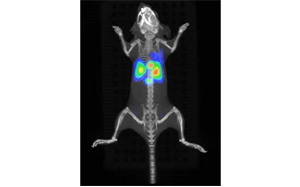

②移植細胞のin vivo可視化:量子ドット技術を利用した移植細胞のin vivoイメージング